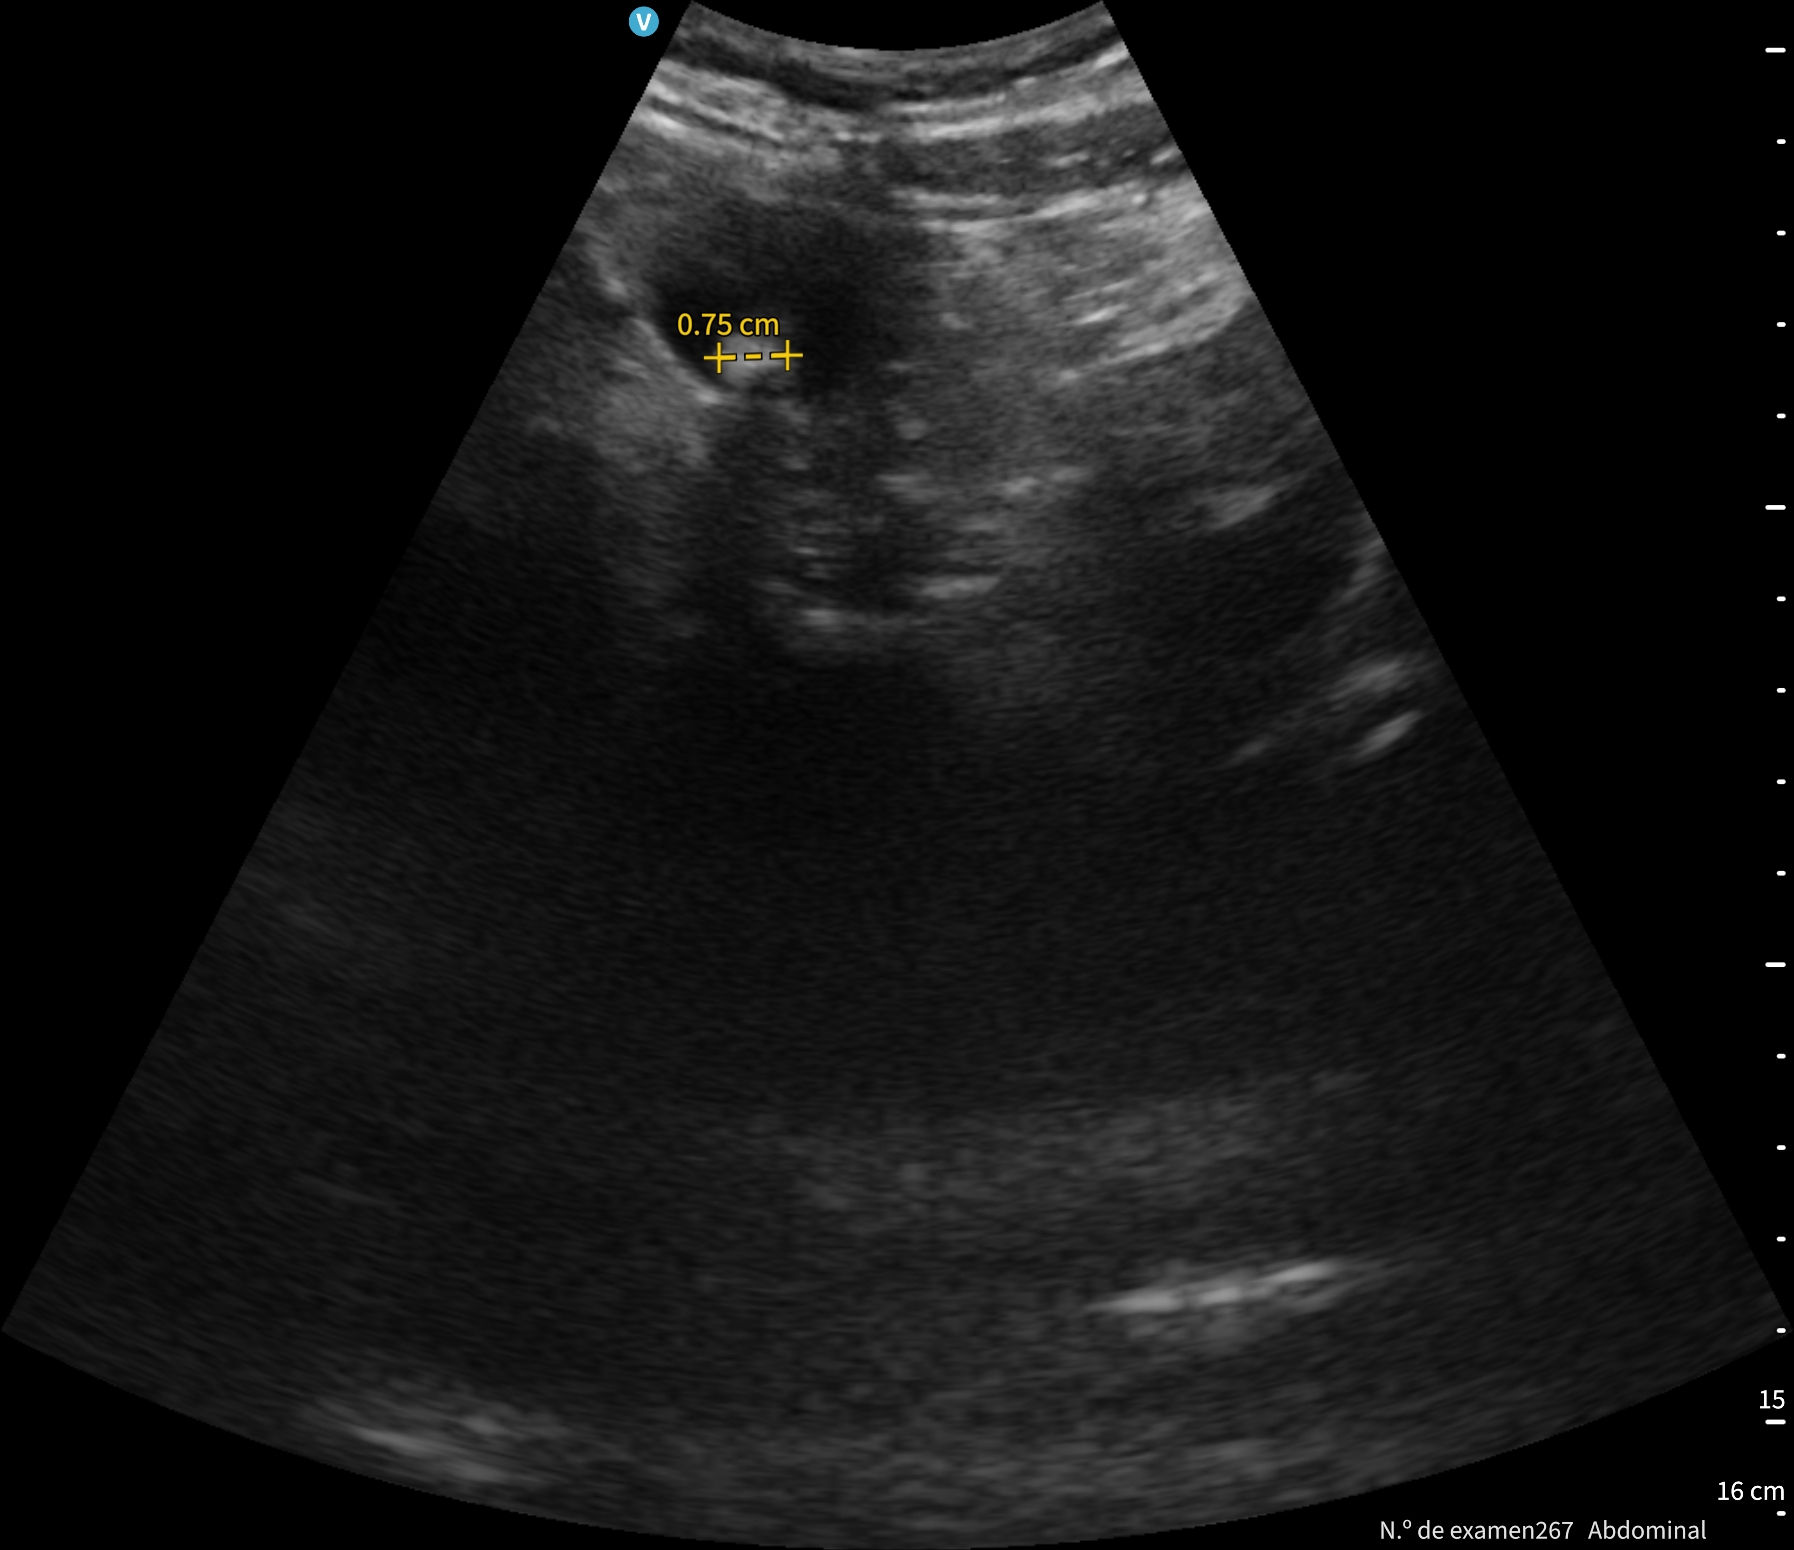

Se le cita en ayunas y realizamos una ecografía abdominal.

En la exploración abdominal se objetiva un cardias laxo de 2,19 cm, y la vesícula biliar distendida con colelitiasis múltiple.